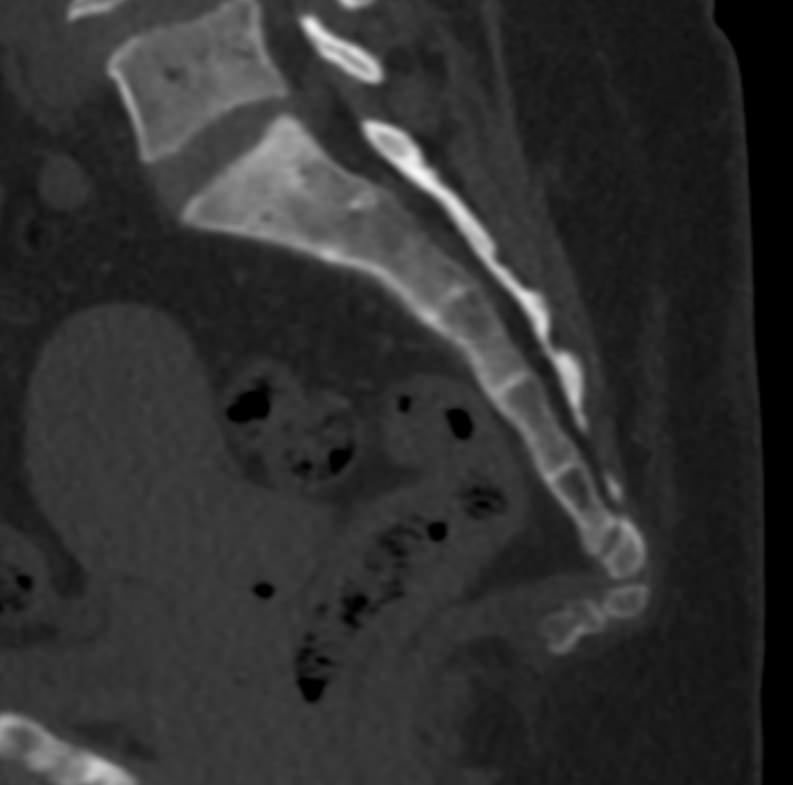

Одним из наиболее информативных методов диагностики заболеваний копчика является мультиспиральная компьютерная томография. Метод основан на использовании рентгеновского излучения и применения инновационных компьютерных программ для детальной визуализации состояния органов и систем организма. Процедура отличается быстротой, безболезненностью и неинвазивностью (то есть проводится без нарушения целостности кожи и расположенных под ней тканей).

В наших центрах обследование копчика выполняется на современных мультиспиральных томографах TOSHIBA AQUILION, оснащенных увеличенным количеством сверхчувствительных детекторов, позволяющих производить 64 или 128 срезов с минимальной толщиной от 0,5 мм.

Инновационные возможности аппаратов дают возможность получить множество послойных снимков высокого качества и реконструировать на их основе трехмерную модель органа. Кроме того, аппаратура позволяет за счет сокращения времени сканирования максимально уменьшить лучевую нагрузку на пациента.

Что покажет КТ копчика

- перелом крестца или копчика, смещение позвонков и другие травмы, в том числе застарелые.

- кисты копчика.

- дегенеративно-дистрофические патологии позвоночника – остеохондроз и другие.